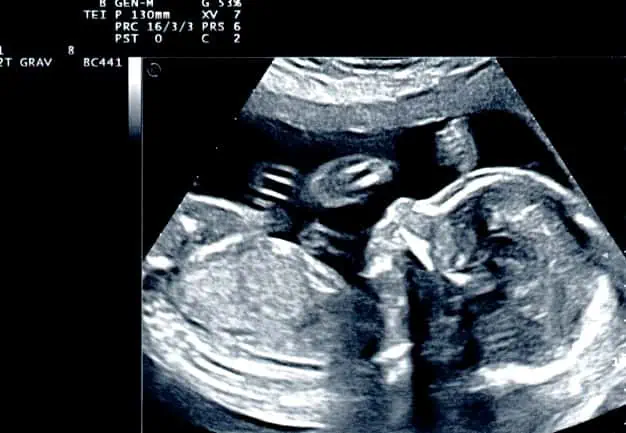

در دوران بارداری سونوگرافی کاربردهای بسیاری برای مادر و جنین دارد که در این قسمت از نمناک به برخی از این موارد اشاره خواهیم کرد :

سونوگرافی به بررسی سقط جنین و تشخیص بیمارانی که در خطر سقط، بارداری خارج رحمی و مرگ جنین قرار دارند ، کمک می کند.

3- بررسی ناهنجاری های مربوط به جنین :

تنها راه تشخیص ناهنجاری ها و اختلال در شکل بدن جنین ، با سونوگرافی است.

برخی ناهنجاری هایی که می توان نام برد ، عبارتند از :

تشکیل نشدن مغز ، شکل نادرست در ستون فقرات ، بزرگ بودن سر جنین ، اختلالات کلیوی و گوارشی.

سونوگرافی در ماه های مختلف بارداری انجام می شود و نسبت به سایر آزمایشات کم خطر تر است اما بهترین درمان برای آن ، بین هفته های 18 تا 20 است.

اما برای تشخیص بارداری دوقلویی یا چند قلویی وجود جنین یا بارداری پوچ شکل نگرفتن مغز و سایر ناهنجاری قبل از هفته 12 نیز توصیه می شود.